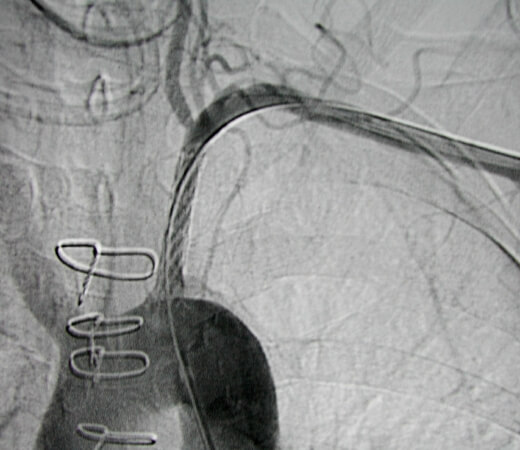

Once access was achieved across the occlusion, a long sheath was placed from the common femoral artery across the occlusion. -

Final image after placement of a balloon expandable stent demonstrating restored patency of the proximal left subclavian artery.

Comment: Given the left subclavian artery occlusion at the origin with almost none of the occluded vessel evident on the thoracic aortogram, it was best to gain upper extremity arterial access to facilitate the attempt at crossing the occlusion. Once we were able to cross the occlusion, we didn’t want to place the sheath needed for stent placement. Therefore, we used a snare to capture the guidewire and ultimately placed a balloon-expandable stent across the occlusion from a common femoral artery approach.